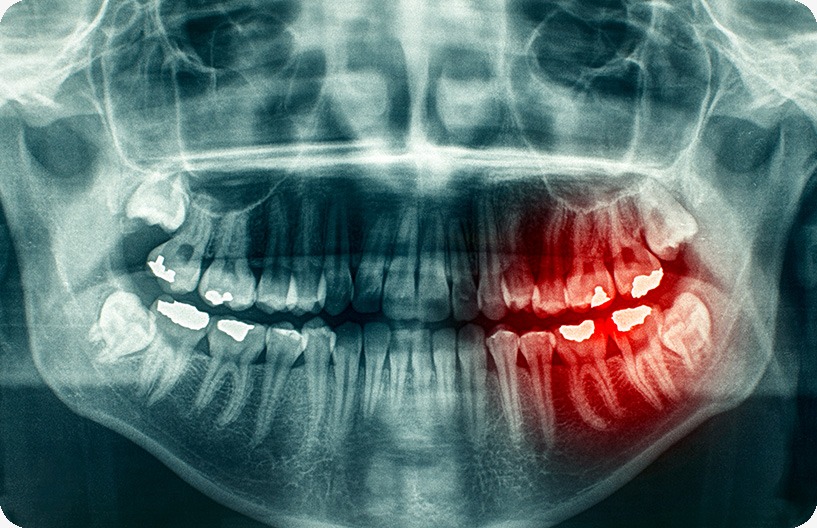

Oftentimes there is not enough room to accommodate wisdom teeth, which can impede their ability to grow into the mouth correctly. For some people, the wisdom teeth only partially emerge through the gums, which can result in cavities, crowding issues with the surrounding teeth, gum infections, and/or severe pain. When they are first developing, the wisdom teeth may begin to grow in an unusual direction. This uneven development may be responsible for several problems, including crowding and damage to the adjacent second molars. When there is not enough space for the wisdom teeth to erupt into your mouth at all, this is known as ‘Impacted Wisdom Teeth.’ When wisdom teeth are impacted in the jaw, the opening around the teeth may become a fertile ground for bacteria to start developing, leading to infection in the gum tissues causing severe discomfort, swelling, pain, and illness. Early removal of impacted wisdom teeth is often recommended to avoid future problems and to avoid costly surgical procedures.

Through the use of digital x-rays and a full and complete oral exam, Donsdale Dental will be able to perform a thorough examination of your teeth and gums to determine exactly what is going on in your gums and bone tissue and decide if an extraction is required.